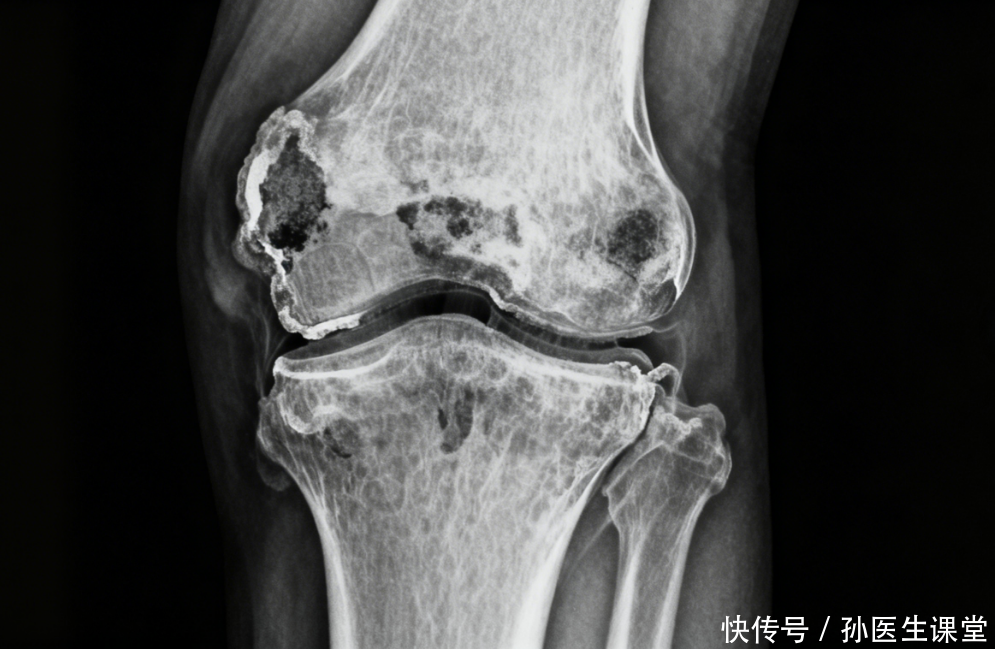

忽视身体信号的"鸵鸟心态"不少患者只有在痛风发作时才急忙就医,疼痛一消失就又变回"逍遥派"。这种"鸵鸟心态"使得痛风得以在体内悄悄"布局",从偶尔的急性发作,逐渐演变成慢性关节炎,甚至形成痛风石,损害肾脏。